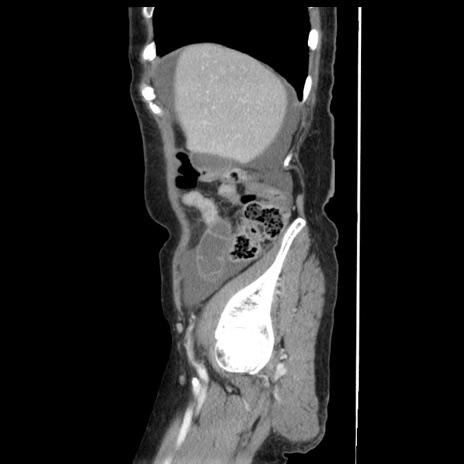

症例1(矢状断像)

【症例】80歳代女性

【主訴】腹痛

【現病歴】8時間前から腹痛あり来院。

【既往歴】糖尿病、脂質異常症、子宮体癌にて子宮全摘術

【身体所見】意識清明・会話良好だが腹痛で苦悶様、全腹部にわたって反跳痛と圧痛あり

【データ】WBC 13600、CRP 0.14、LDH 224、CK 90